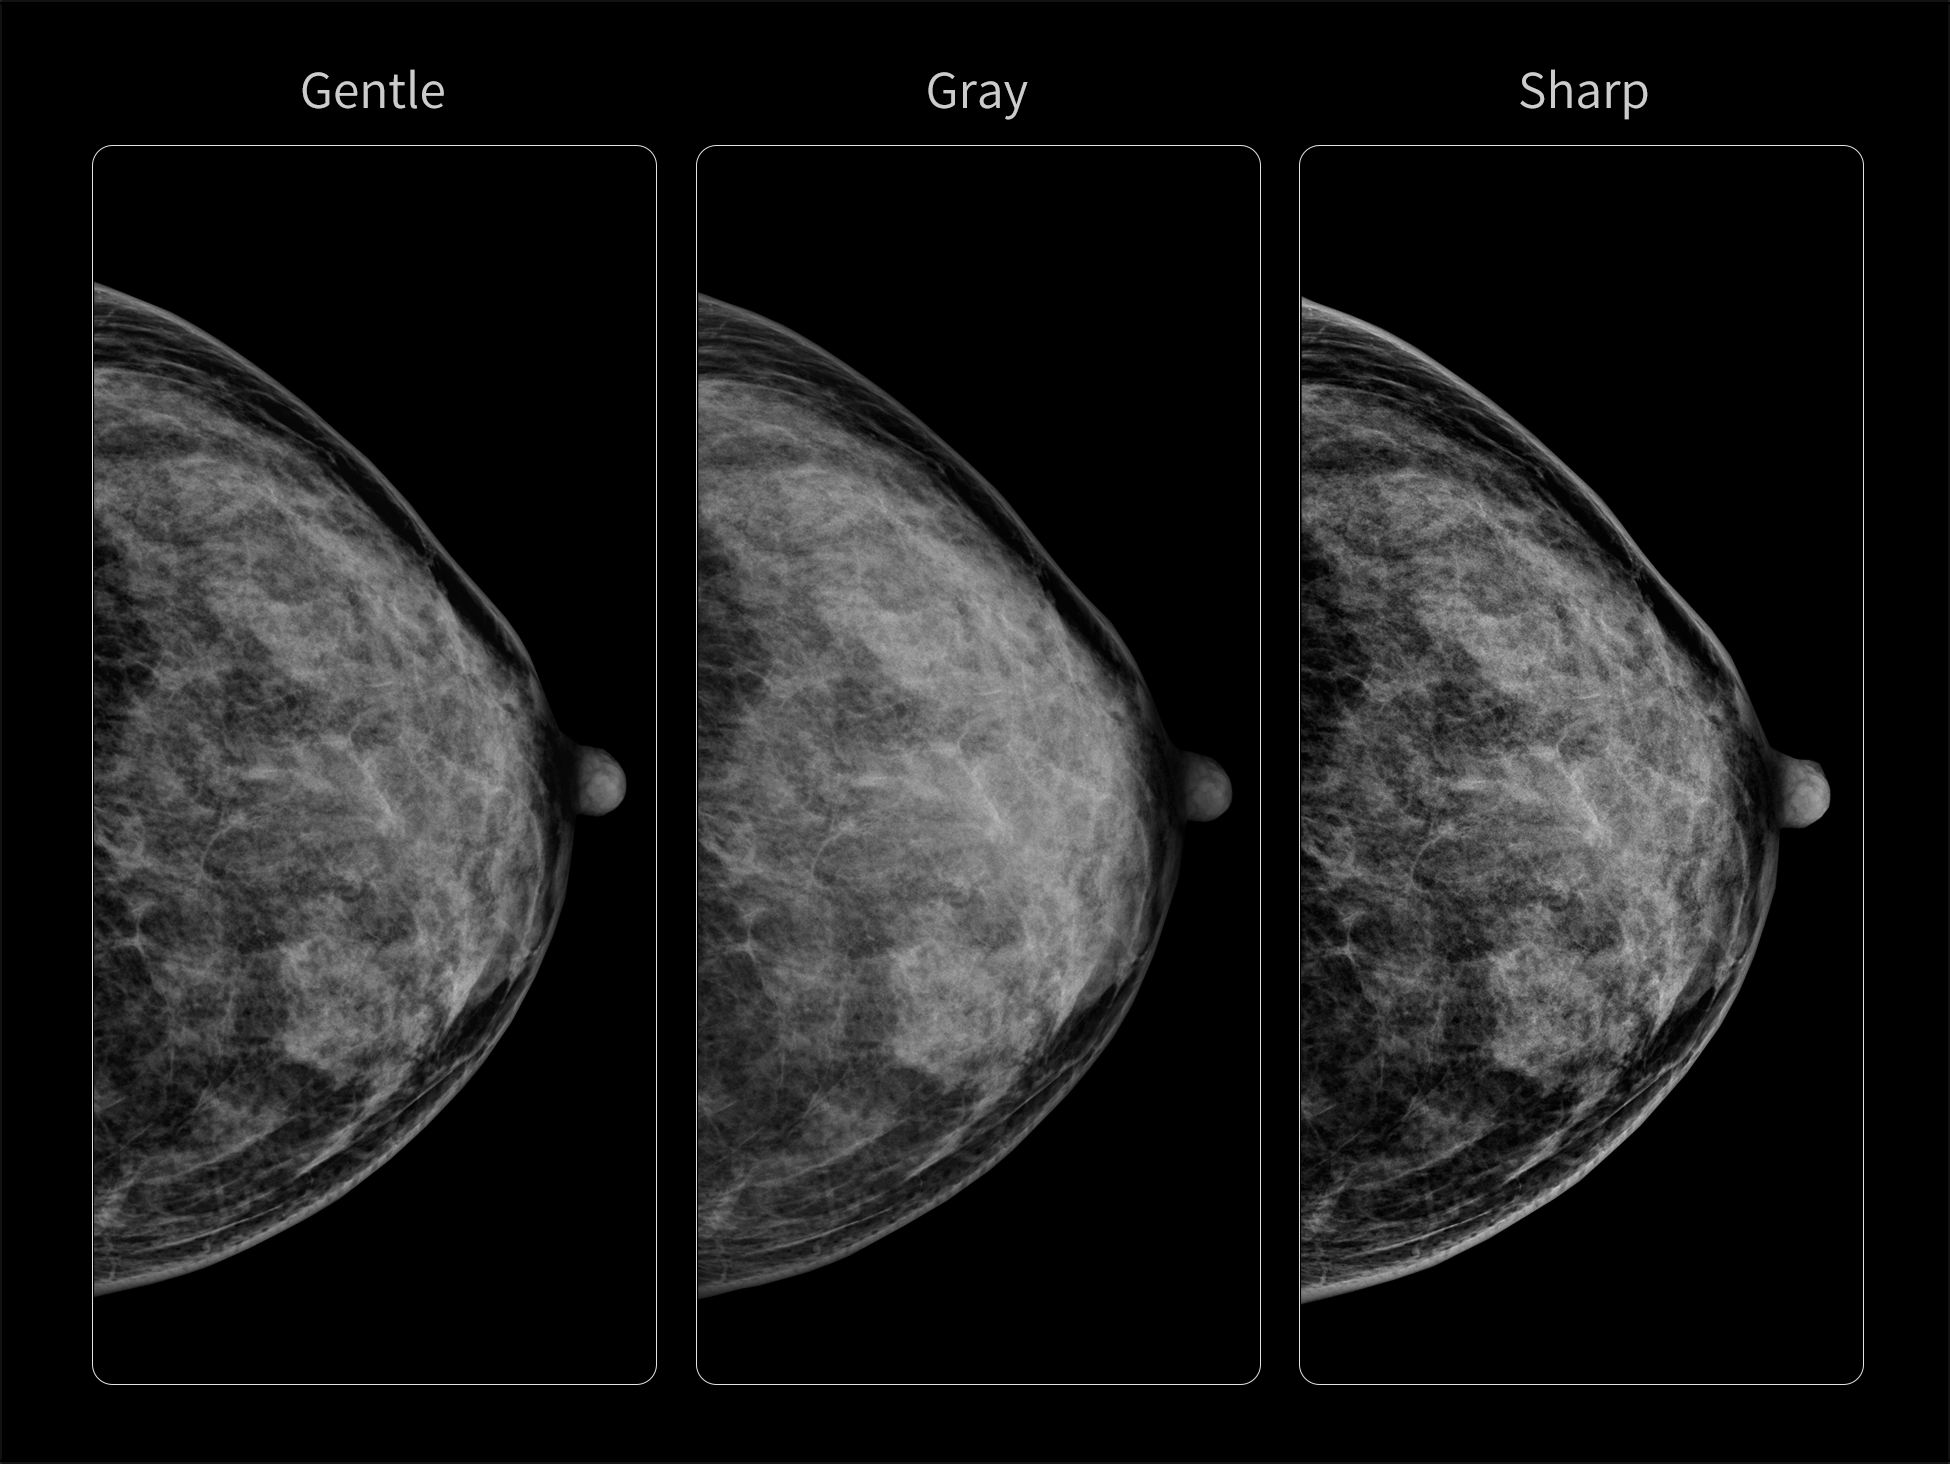

- Consistent Clarity